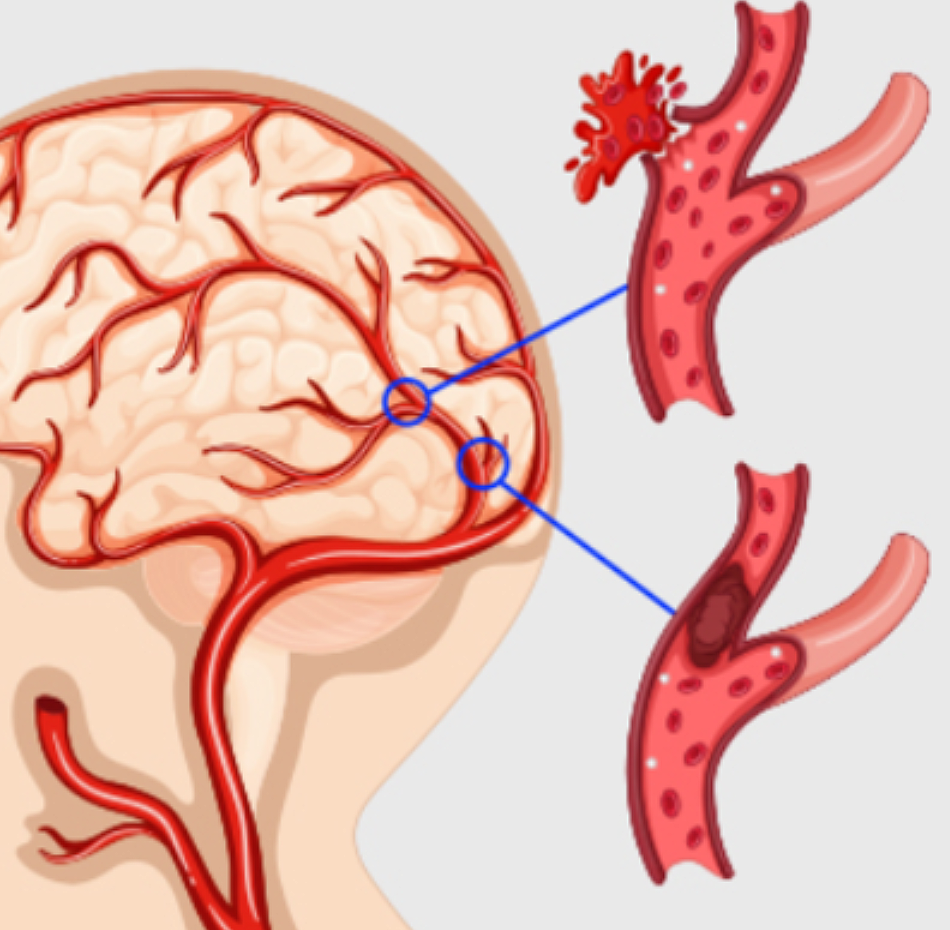

뇌졸중은 뇌 일부분에 혈액을 공급하는 혈관이 막히거나 터지면서 뇌가 손상돼 신경학적 이상이 나타나는 병입니다. 밤과 낮 그리고 실내외 온도 차가 계절에는 혈압 상승과 혈관 과부하로 심뇌혈관 질환 발병 우려가 매우 높습니다.

뇌에 혈액을 공급하는 혈관이 막히게 되면 뇌의 일부가 손상되는 ‘뇌경색 증상’, 뇌혈관이 터져 주변 뇌가 손상되는 ‘뇌출혈 증상’이 있습니다. 두 질병 모두 사망에 이르거나 뇌손상으로 인한 후유증이나 신체장애를 남길 수 있는 위험한 질환입니다.